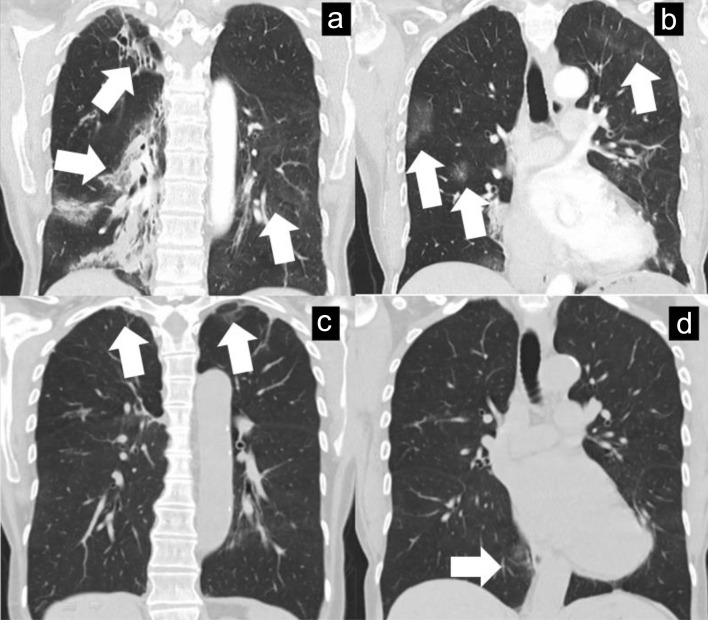

Immunocompromised patients, especially those receiving B-cell depleting therapies, are at risk for developing atypical presentation with regard to severe acute respiratory syndrome coronavirus 2 (SARS-CoV-2) infection, with the potential for diagnostic delay and adverse outcomes if such delay occurs. A 66-year-old female with history of granulomatosis with polyangiitis (GPA) with previous pulmonary involvement, treated with rituximab and low-dose prednisolone, presented with prolonged fever and cough after having been treated at home for a mild SARS-CoV-2 infection in early July 2023. The patient had a prolonged course over several months with constitutional symptoms such as fever, cough and malaise. During the investigation, which encompassed a wide range of microbiological and immunological tests, the patient was initially thought to have a flare of GPA which she was treated for without appreciable improvement, then for multiple microbiological organisms without appropriate resolution of the patient's symptoms. The differential diagnosis of prolonged SARS-CoV-2 infection was reconsidered in October 2023, and then confirmed by the presence of SARS-CoV-2 viremia through polymerase chain reaction (PCR) testing of the blood. The patient received a prolonged course of antiviral therapy with complete clinical, virological and radiological resolution. Prolonged SARS-CoV-2 infection with viremia in immunocompromised individuals needs to be considered on the differential diagnosis list in such patients presenting with constitutional symptoms, with PCR testing of the blood as a simple and effective way to establish the diagnosis.

Abstract Image